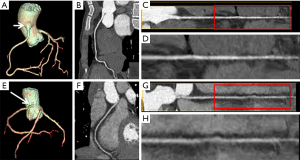

The objective image assessment was performed by the 2 same observers together. For every patient, the aortic (Ao) root was examined at the left main coronary artery level on an axial image. The mean attenuation (CT value) and its standard deviation (SD) in Hounsfield units (HU) of the aorta and adjacent perivascular tissue (PT) on the same slice were measured by placing a region of interest (ROI) on these areas (Figure 1). From these measurements, the signal-to-noise ratio (SNR) and the contrast-to-noise ratio (CNR) for the descending aorta were calculated using the following formula:

For the subjective evaluation, all images in both groups could display all coronary arteries clearly and had strong confidence for diagnosis (Figure 2). The image contrast score (4.56±0.57 vs. 4.78±0.42), overall image quality score (3.67±0.47 vs. 3.44±0.51), and diagnostic confidence (4.74±0.44 vs. 4.74±0.45) had no statistically significant differences (P>0.05) (Figure 3).